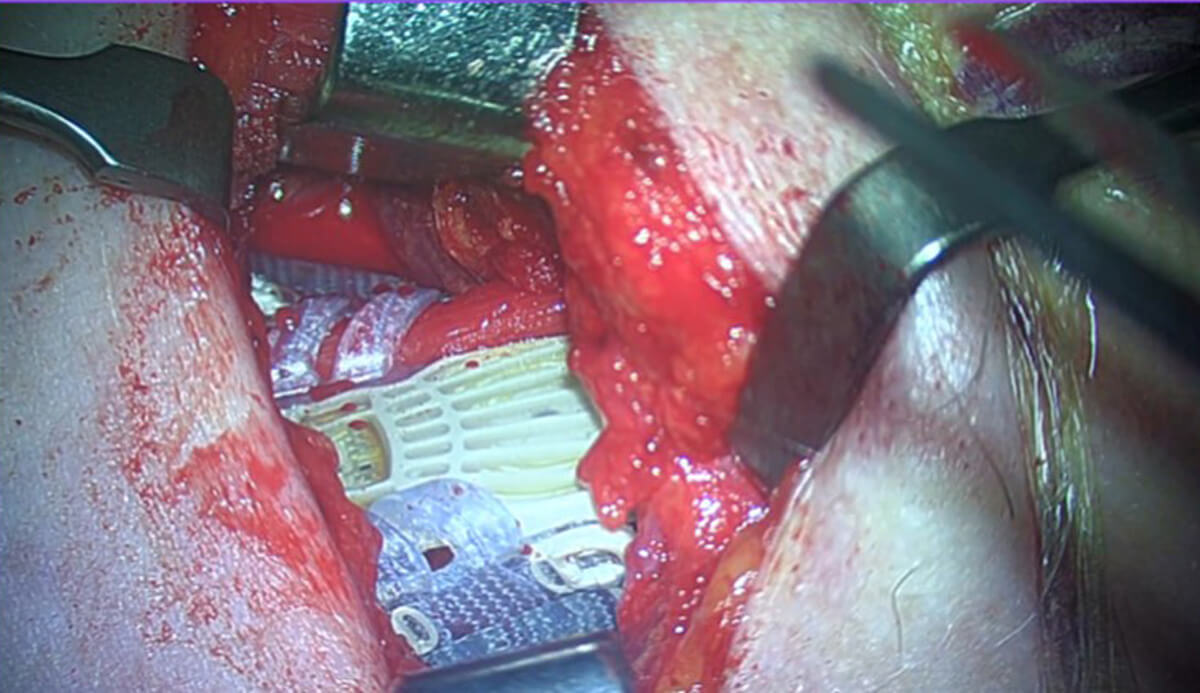

Figure 4: Intraoperative clinical photograph of the first UK Genio Nyxoah implant secured in position overlying the genioglossus muscles and hypoglossal nerves bilaterally.

The surgical procedure involves a submental incision to expose the mylohyoid muscle, followed by dissection to reach the genioglossus muscle and the bilateral branches of the hypoglossal nerve. The implant is then secured in this location, as shown in the diagram (Figure 3) and intraoperative photograph (Figure 4).